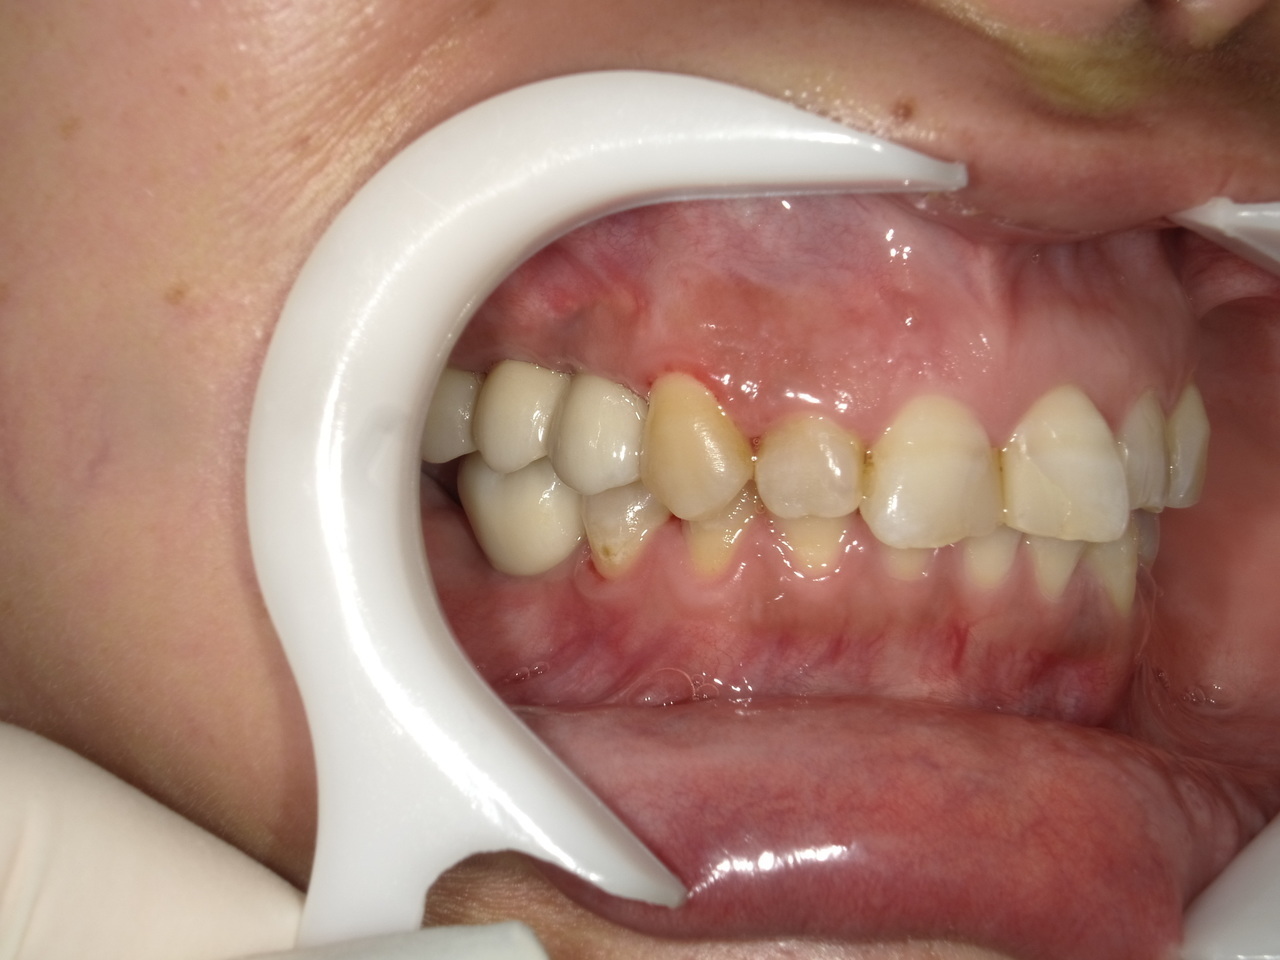

After

枚方市のインプラントの症例

I・K 様 女性 40代

症状としては、左上5の歯根破折を起こしていたため、排膿と自発痛をみとめた。それにともなう骨の大きな欠損。

治療法としては、炎症が強くたったためと、炎症による頬側側歯肉の退縮を認めていたために、まず、抜歯を行い上顎洞内及び歯抜した周囲組織の回復を試みた。その後、患者様がインプラント治療を希望したため、薄い上顎骨に対しては、グラフトレスサイナスリフト、骨欠損部には、人口骨補填を行い、頬側歯肉が退縮していることを改善するために、1回法でリーリングアバットメントを装着して、アバットメントの上に歯肉が覆うようにして、歯肉のボリューム回復を行った。2か月後、インプラントが骨と結合していることを確認して、光学印象を行い、2週間後にアバットメントとジルコニアクラウンを装着した。

治療結果としては、大幅な骨欠損があったが、グラフトレスサイナスリフトと骨欠損部に人工骨を補填して、抜歯した穴が自然に治る状態にしたことで、2か月半という短い期間での治療を完了することができた。(仮に、GBRや通常のサイナスリフトでの治療を行っていたら、最低でも1年は、かかってくる治療であると考える。)また、今回は、即時荷重を避け、1回法での治療を行ったことで、噛めない期間ができてしまったが、1回法で行ったことにより、歯肉のボリュームが増して、ブラッシングがしやすい口腔内環境にすることができた。低侵襲で、短時間で、治療を終えることができ、また、審美性・機能性の回復も行えたことができた。